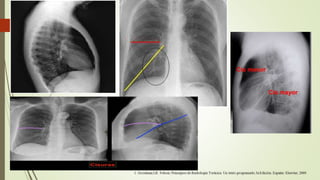

INDICE CARDIOTORACICO

ICT

DIÁMETROS TRANSVERSOS

D =DISTANCIA MAYOR DESDE LA LÍNEA MEDIA DE LA

COLUMNA HASTA EL BORDE CARDIACO DERECHO.

I =DISTANCIA MAYOR DESDE LA LÍNEA MEDIA DE LA

COLUMNA HASTA EL BORDE CARDIACO IZQUIERDO.

T =DIÁMETRO TORÁCICO TRANSVERSO (A NIVEL DE

DIAFRAGMAS)